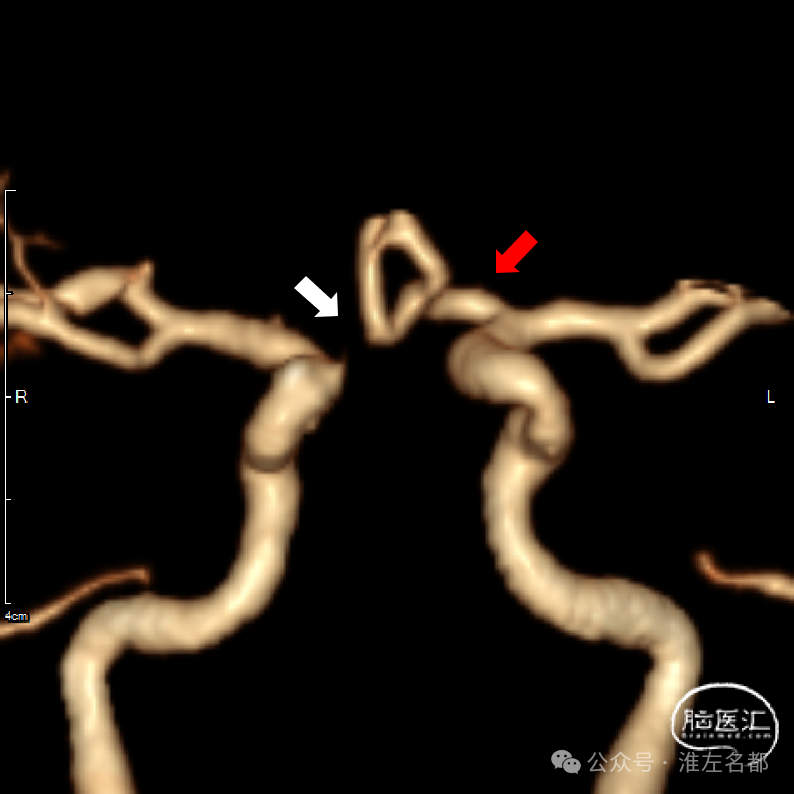

微导管通过闭塞位置,造影证实位于真腔。

经微导管释放取栓支架(S AB 4*20mm)后造影,前向血流恢复,局部狭窄(红箭)。

回收取栓支架后造影:闭塞再通,右侧A2局部轻微狭窄,但A3-4交界处可见造影剂渗出,提示出血。

予以降压等处理,约5分钟后造影提示出血已经停止。

取出少量血栓

术中DSA平板CT示:前纵裂旁少量蛛网膜下腔出血。